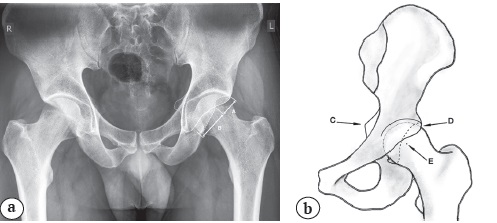

Важным диагностическим моментом является оценка соотношения переднего и заднего краев вертлужной впадины. В норме на рентгенограмме таза передний и задний края вертлужной впадины не пересекаются, а задний край проходит через центр ротации головки бедренной кости. Одним из вариантов строения является пересечение передней и задней стенками с правильной ориентацией задней стенки, названный признаком перекреста (cross-over sign). В этой ситуации имеет место выступающий передне-верхний край вертлужной впадины, снижающий объем сгибания и внутренней ротации в суставе. Однако чаще при наличии пересечения передней и задней стенок встречается ретроверсия вертлужной впадины. При этом визуализируется знак перекреста, а задняя стенка вертлужной впадины расположена медиальнее центра ротации головки бедренной кости [37, 38]. Нередко при ретроверсии вертлужной впадины можно увидеть выступающую седалищную ость (рис. 3) [39, 40].

Рис. 3. Двухсторонняя ретроверсия вертлужной впадины:

а — индекс ретроверсии = А/(А+В) × 100;

b — схематичное изображение ретроверсии вертлужной впадины.

C — седалищная ость; D – передний край вертлужной впадины; E — центр ротации, пунктиром обозначена задняя стенка вертлужной впадины, проходящая медиальнее центра ротации головки

Fig. 3. Bilateral acetabulum retroversion:

a — retroversion index = A/(A+B) × 100;

b — schematic view of acetabulum retroversion.

C — sciatic spine; D — anterior edge of the acetabulum; E — center of rotation, dotted line indicates posterior wall of the acetabulum, passing medial to the rotation center

В литературе не удалось найти точное значение индекса ретроверсии (отношение расстояния от верхнего края вертлужной впадины до пересечения переднего и заднего краев впадины к общей длине вертлужной впадины и умноженное на 100), при котором выполнение артроскопии противопоказано. Однако отдельные исследования, в которых изучались результаты феморопластики в условиях ретроверсии вертлужной впадины, показали плохие результаты в 33,8% наблюдений [41]. В другом исследовании был получен хороший результат у пациентов с величиной средней ретроверсии 35,1% [42]. Вероятно, вопрос об ограничении показаний к артроскопии при ретроверсии вертлужной впадины должен рассматриваться не только исходя из величины индекса ретроверсии, но и на основании других анатомических факторов, в т.ч. угла сферичности головки бедренной кости.